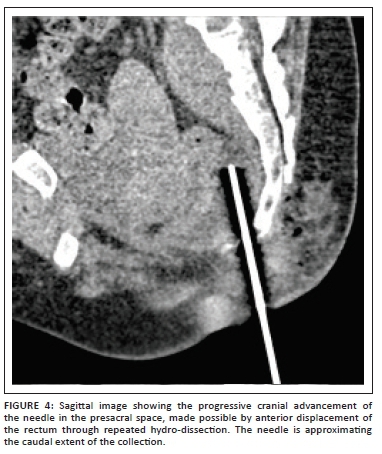

The spinal needle was then withdrawn and then re-inserted from a para-median point (to avoid injury to the midline ano-coccygeal ligament) to the same vertical level after infiltration with local anaesthetic. The needle was carefully advanced cranially and hydro-dissection was repeated with 20 mL saline to further displace the rectum anteriorly. This was repeated until the needle could reach the target point (Figure 4).

As the collection was viscous and deep, an 18 G co-axial needle was chosen and was introduced utilising the spinal needle as a guide. Upon confirmation of accurate needle placement, the spinal needle was removed and the co-axial system was further advanced cranially into the collection (Figure 5). Upon removal of the stylet, 4 mL - 5 mL of thick purulent material was aspirated, placed into sterile containers and sent for histo-pathological confirmation and a cartridge-based nucleic acid amplification test (CB-NAAT).